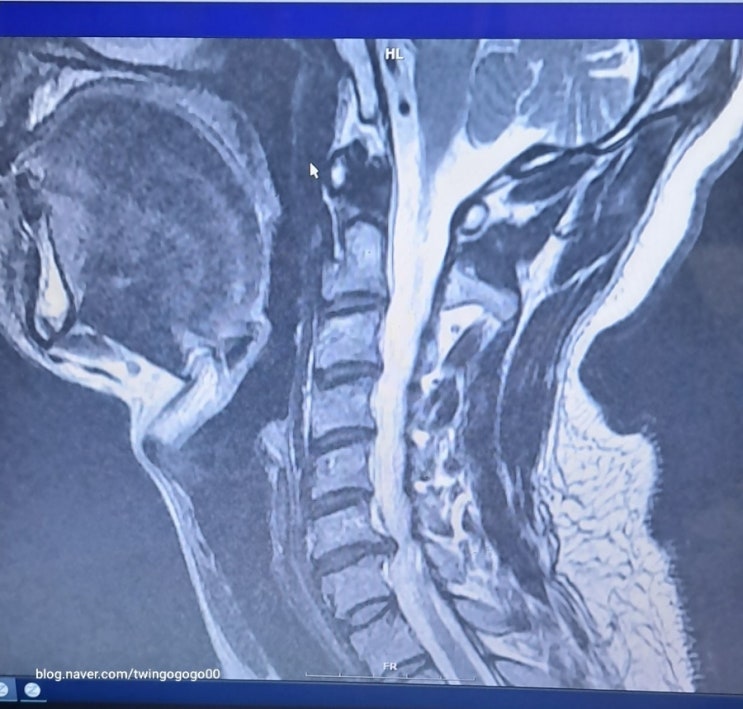

목디스크 증상 난청 이명 어지럼증 등 견갑골 날개뼈 팔 방사통증

목디스크 1~2번 / 2~3번 이명 난청 현기증 어지러움 두통 목디스크 4~5번 / 5~6번 / 6~7번 견갑골 날개뼈 ...